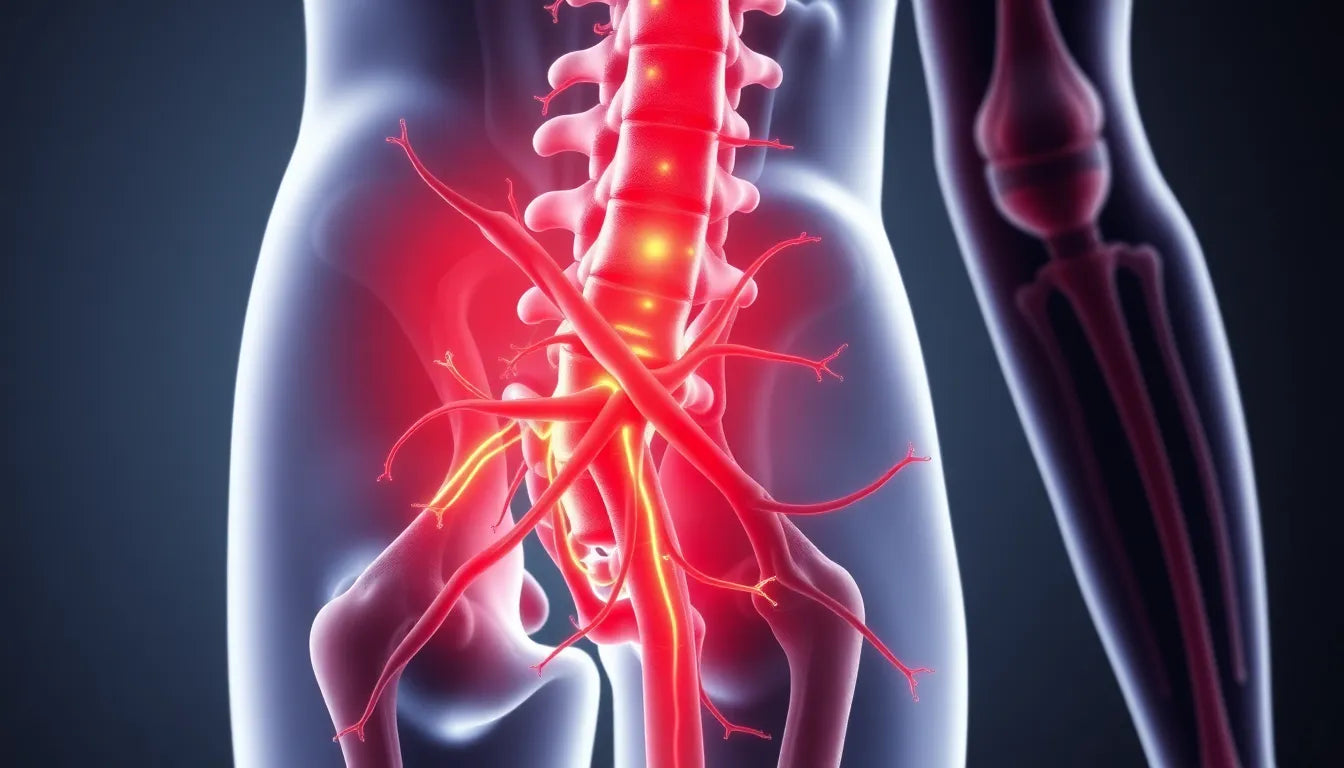

Tijdens de zwangerschap ondergaat het lichaam van een vrouw talloze veranderingen om zich aan te passen aan de groei van de baby. Een van de meest voorkomende problemen is de toename van het lichaamsgewicht, wat extra druk uitoefent op de wervelkolom en de heupzenuw. Deze druk kan leiden tot sciatique, die zich manifesteert als een scherpe, brandende pijn die uitstraalt van de onderrug naar de bil en het been. Het is niet ongebruikelijk dat deze pijn verergert door activiteiten zoals zitten, staan of zelfs hoesten.

De ontwikkeling van sciatique tijdens de zwangerschap kan voornamelijk worden toegeschreven aan de groeiende baby, die extra druk uitoefent op de heupzenuw. Naarmate de baby groeit, vooral vanaf de tweede maand, kan deze druk toenemen, met een piek rond de zesde maand. Dit kan leiden tot een reeks symptomen die variëren van een scherpe, brandende pijn in de onderrug, bil of dij, tot een uitstralende pijn die soms zelfs de enkel bereikt. Deze symptomen worden vaak verergerd door activiteiten zoals langdurig zitten, staan of zelfs eenvoudige inspanningen zoals hoesten.

Sciatique is een aandoening waarbij de heupzenuw onder druk komt te staan, wat resulteert in pijn die uitstraalt van de onderrug naar de benen. Tijdens de zwangerschap neemt het risico op sciatique toe door de extra belasting van de groeiende baby op het lichaam van de moeder. Deze druk kan leiden tot irritatie van de heupzenuw, wat de veelvoorkomende symptomen van sciatique veroorzaakt.